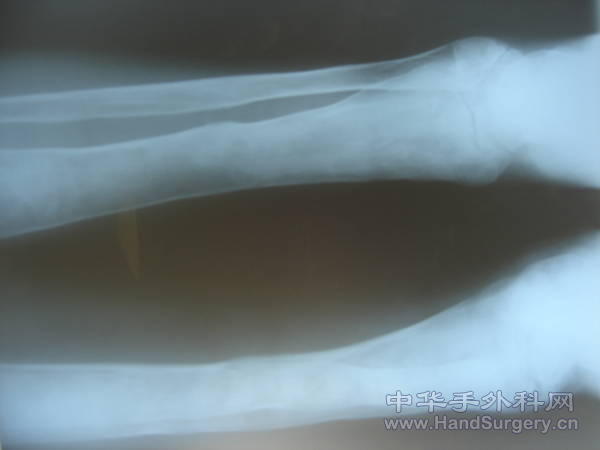

骨纤维异样增殖症

骨纤维异样增殖症,股骨干裂纹骨折!

这是我7年前的一个患者,是个20多岁的小伙子,电脑工程师,摔一跤致右股骨干裂纹骨折而来我们医院住院,我们都从没看过这种病,他全身的骨都变形了,特别是面颌骨,脸型像个脸盘那么大。来到我们科住院我们只能叫他卧床了,也不知其他的治疗方法,问了他病史及治疗经过,他说从小就得这病,一直在广州一个军区医院的老医生那开一种口服药治疗,具体药名不记得了,目前好象这病没法根治了,只是对它引起的并发症进行对证处理了!